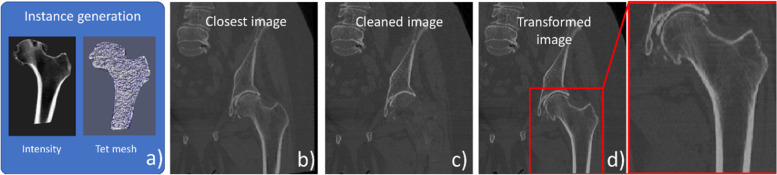

The aim of the augmentation method is to generate diversified and realistic images to train a machine learning approach. In standard augmentation for supervised learning, we generate new image samples from a collection of training images with corresponding labels, i.e., in our application segmentation masks for our four bones (left/right proximal femurs and hip bones). For a given structure, a new image is created as follows (Fig. 1):

Constrained random sampling of a tetrahedral mesh with embedded image intensities using the SSIM (Fig. 1a)

Selection of the closest image in the training set based on an affine distance criterion between the sampled mesh and the corresponding mesh of the closest image (Fig. 1b)

Cleaning of the closest image by “removing” the intensities of the corresponding bone (Fig. 1c)

Warping of the cleaned image using thin-plate spline (TPS) and rigid transformations along with the “painting” of the sampled synthetic image intensities (Fig. 1d)

The main steps of a new computed tomography image generation exemplified with the left proximal femur. Random sampling of instance using a statistical shape and intensity model (SSIM) (a). Selection of closest image based on shape affine similarity (b). Cleaning of corresponding structure in the closest image (c). Geometrical transform of cleaned image with painting of instance intensities (d)